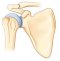

Soit la coiffe très abimée ou absente

au quel cas on mettra en place une prothèse inversée. Qui permet par sa forme de suppléer aux tendons absents.

soit la coiffe est conservée et de bonne qualité,

ce qui est rare dans le contexte avec des patients souvent multi-infiltrés, alors on met en place une prothèse standard totale ou partielle

Deux solutions s’offrent alors à nous: